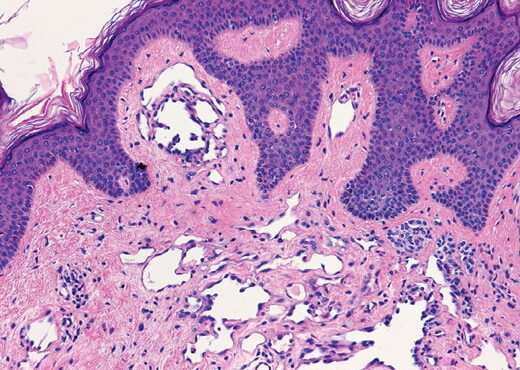

Atrophic lichen planus = الحزاز المنبسط الضموري